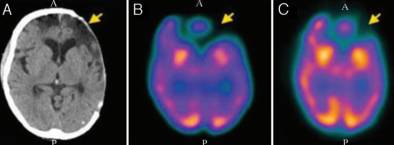

结果显示,颅骨成形术前,9例(26.5%)患者的GOS评分为5分,25例(73.5%)GOS评分为4分;颅骨成形术后,34例(100%)患者GOS评分为5分,较术前提高。各项认知测试结果表明,35.3%-90.9%的患者于颅骨成形术后认知功能改善(表1)。此外,94%患者的脑SPECT成像结果提示,在不同脑叶中脑灌注情况均得到改善(图1-4)。

图4. A.颅脑CT显示左侧颅骨缺损;B.颅脑SPECT示术前脑血流灌注低;C.颅脑SPECT示术后脑血流灌注较术前改善。